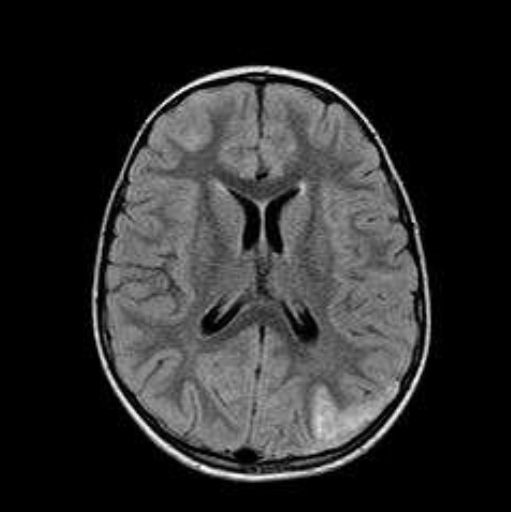

Alla RM encefalo si evidenzia una alterazione a margini sfumati senza enhacement a livello di nuclei dentati, porzione posteriore del ponte, nuclei subtalamici, talamo anteriore, teste dei nuclei caudati, ginocchio del corpo calloso, insule, della regione temporo-mesiale bilaterale, frontale, parietale posteriore e dei centri semiovali. I reperti coinvolgenti la sostanza bianca sottocorticale e i gangli della base in modo asimmetrico sono compatibili con riacutizzazione di processo infiammatorio (ADEM), per cui si imposta terapia con metilprednisolone (30 mg/kg in bolo) per 4 giorni seguito da prednisone per os con riduzione graduale in 4 settimane. La bambina presenta rapida risposta clinica e normalizzazione dell’EO e dell’EEG. Viene dimessa affidandola alla Neurologia per evidenziare una eventuale disseminazione spaziale-temporale delle lesioni, che sarebbe compatibile con una sclerosi multipla a esordio pediatrico.